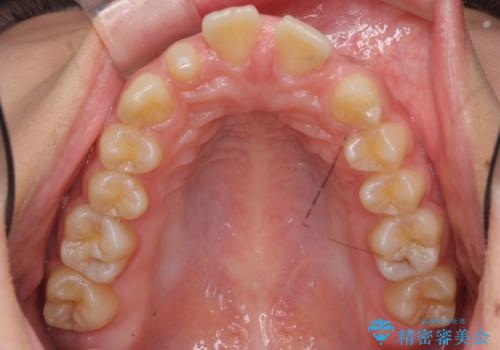

- 前歯の並びを主訴に来院。

前歯が出ており、また、左上の側切歯が1本生まれつき少ない状態でした。

また、右の奥歯の関係も上が前にある状態で大きくずれていました。

今回は左右とも1歯対2歯の関係であるため、それは変えずに前歯を可及的にひっこめて足りない部分をブリッジで補う治療としました。

奥歯の関係を完全に1級にするには右上の小臼歯の抜歯が必要でしたが、もともと左上の前歯が生まれつき少ないため今回は歯を抜かずに治療しています。